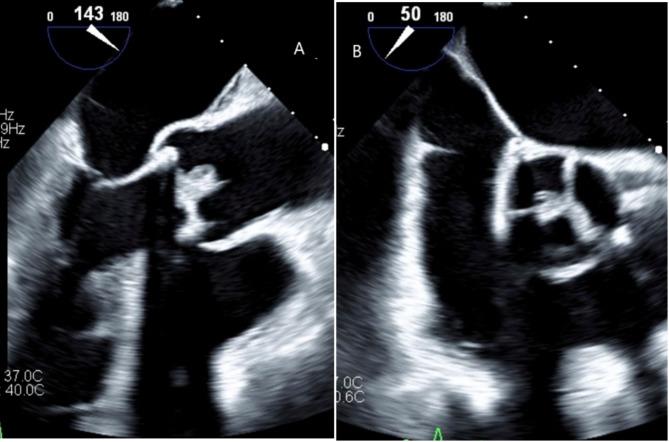

Histoplasma capsulatum infective endocarditis (IE) is rare and often fatal, especially in prosthetic valve patients, due to delayed diagnosis and limited therapeutic options. This case demonstrates the utility of AngioVac for managing large fungal vegetations, underscores the importance of considering fungal IE in culture-negative cases, and highlights the role of a multidisciplinary approach in high-risk patients. We report a 76-year-old female with a bioprosthetic aortic valve who presented with persistent culture-negative fever, splenic infarcts, and large vegetations on her prosthetic valve. Extensive diagnostic workup confirmed fungal endocarditis after AngioVac-assisted debulking revealed H. capsulatum on tissue cultures. Despite prompt initiation of antifungal therapy and multidisciplinary management, her course was complicated by recurrent embolic events, septic shock, and eventual death.

荚膜组织胞浆菌感染性心内膜炎(IE)较为罕见且往往致命,尤其是在人工瓣膜患者中,原因是诊断延迟且治疗选择有限。本病例展示了AngioVac在处理大型真菌赘生物方面的效用,强调了在培养阴性病例中考虑真菌性IE的重要性,并突出了多学科方法在高危患者中的作用。我们报告一名76岁女性,她植入了生物人工主动脉瓣膜,出现持续培养阴性的发热、脾梗死以及人工瓣膜上的大型赘生物。广泛的诊断检查在AngioVac辅助减容术后组织培养发现荚膜组织胞浆菌后确诊为真菌性心内膜炎。尽管及时开始抗真菌治疗并进行多学科管理,但她的病程因反复栓塞事件、感染性休克及最终死亡而复杂化。